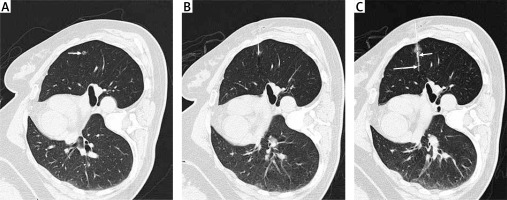

Patient positioning was determined based on the location of the target LN(s) (Photo 1 A). A needle pathway was selected so as to minimize the distance between the skin and the LN, after which a 21G introducer needle (Argon Medical Devices, Inc, TX, USA) was inserted into the lung parenchyma until the tip of the needle was within 10 mm of the target nodule (Photo 1 B). After CT-based confirmation of optimal needle positioning, the HW was released. Postoperative CT imaging was used to confirm appropriate HW localization and to detect any procedure-related complications.

VATS wedge resection (WR) procedures were performed under general anesthesia within 3 h following localization. A 3–5 cm incision in the chest wall was made, after which WR was performed based on HW visualization or IG fluorescence (Photo 2 C). The WR range was at least 2 cm from the localized area of the lung. Rapid intraoperative pathological analyses of the resected LN sample were then conducted. When LNs were confirmed to be invasive lung cancers, lobectomy and systematic lymph node resection were performed. The systematic lymph node dissection was performed according to the National Comprehensive Cancer Network guideline [13].